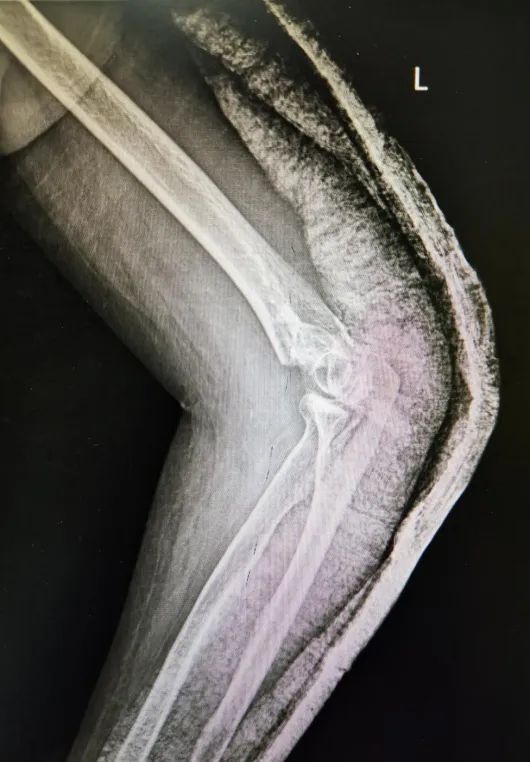

骨折是临床上最常见的疾病,这不,今年1月份的一天,邵女士下楼走台阶时不慎摔倒,伤及左肘,当时感觉疼痛剧烈,立即就诊于北京燕化医院急诊科,查X片提示:左肱骨髁间骨折(闭合性),进一步完善相关检查,一周后顺利接受了手术治疗。

在这种传统观念的影响下,4周过去了,邵女士的胳膊不仅仍肿胀疼痛,而且还屈伸两难,为了早一点恢复,她再次就诊于北京燕化医院康复医学科,经查体:左肘关节及周围组织肿胀明显,左肘关节活动度(-50°)-90°,活动范围明显受限,康复医学科医生和技师给予制定了详细的康复治疗计划,4周后左肘关节活动度达到了(-15°)-100°,胳膊不仅能屈,也能伸了,肿胀疼痛也消失了,还能双手配合做一些家务劳动,邵女士也露出了高兴的笑容,每天都积极的来康复科治疗。